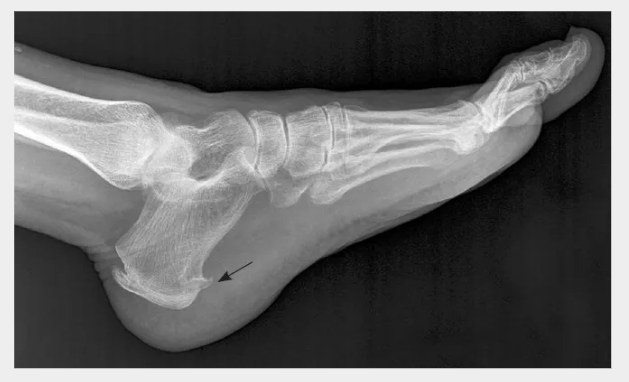

족저 근막염은 발바닥에 있는 두꺼운 섬유조직인 족저근막에 염증이 생겨 발뒤꿈치와 발바닥에 통증을 유발하는 질환입니다. 이 질환을 이해하고 적절한 치료와 예방 전략을 통해 효과적으로 관리하는 방법을 알아보겠습니다.

🔵 발뒤꿈치 안쪽의 통증: 족저근막염은 발뒤꿈치 안쪽에서 주로 통증을 유발합니다. "왜 발뒤꿈치가 이렇게 아프지?" 하고 생각되신다면 족저근막염을 의심해볼 수 있습니다.